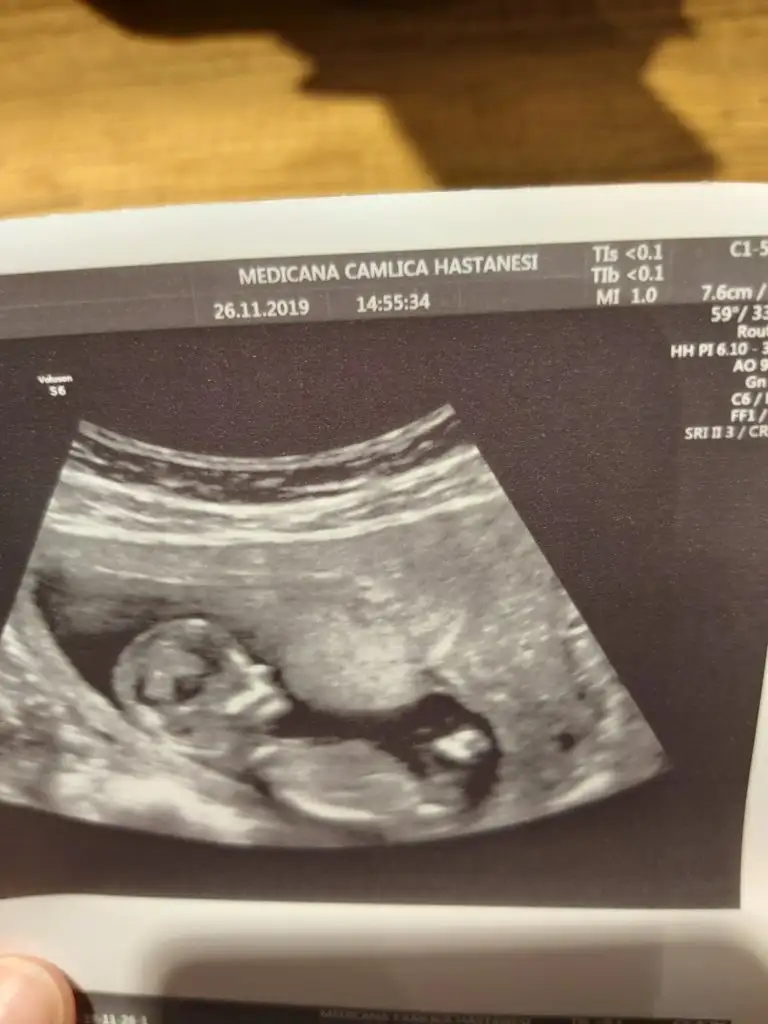

Bana da de banada attım resminiaaa nuba göre erkek canm kaç haftalıktı bu usg

Erkek mi ki acabaTeyzeler bu da bizim fotomuz ☺